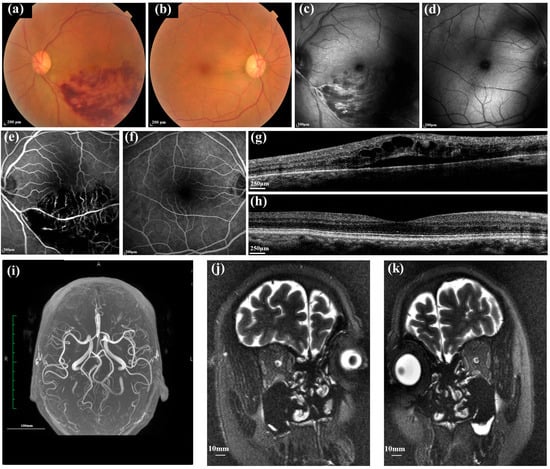

2.2. Eye Examination

2.3. Cerebrovascular Evaluation

2.3.1. Measurement of Cerebral Blood Vessel Geometric Parameters

2.3.2. Measurement of the Optic Nerve Sheath and Optic Nerve Diameter, and ONSASW